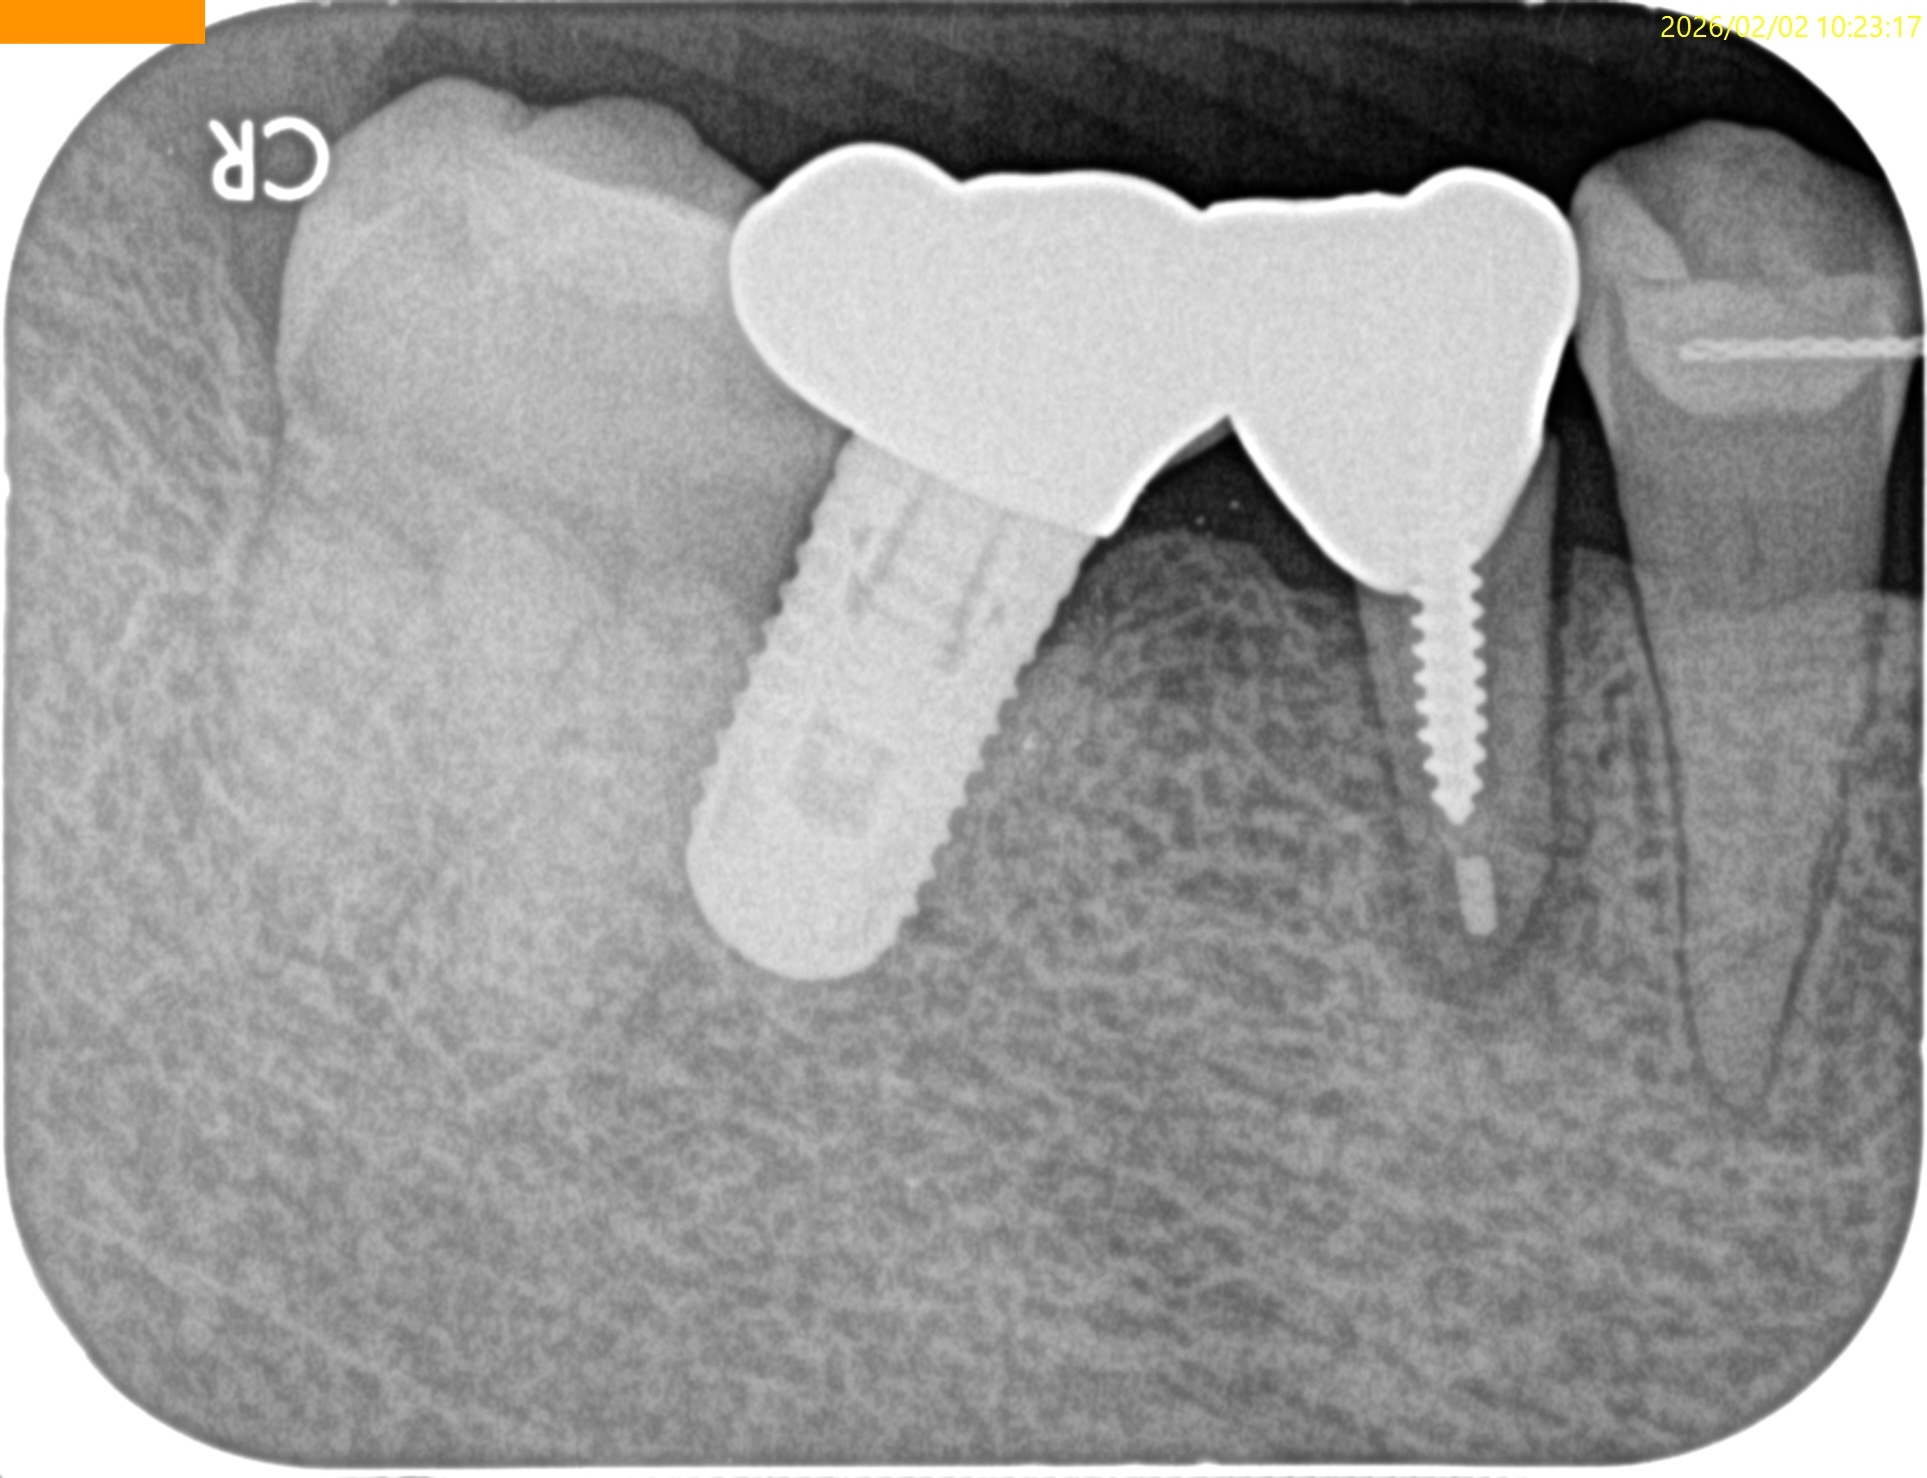

Pre-op Endo Test(2026.2.2)

#29のMBに5mmの歯周ポケットがある。

#29には歯根を取り囲むJ-Shaped lesionがあり、歯根破折の可能性があることを惹起させる。